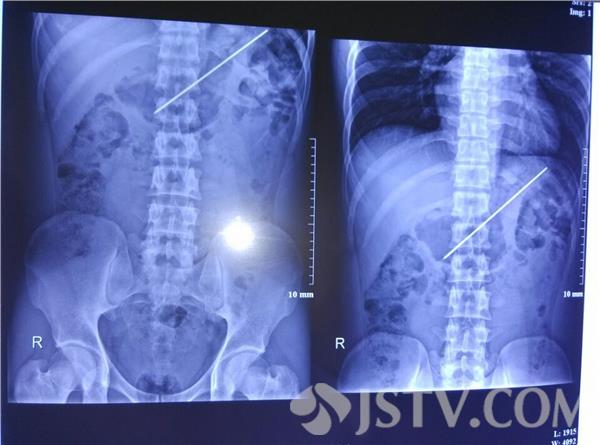

日前,南京解放军第八一医院胃镜室内,主任文卫和同事们紧张地抢救一位吞下烤肉钎子的青年小伙。5分钟后一根长度18cm的钎子成功地从患者胃内取出,患者术后一切生理指标正常,当日痊愈出院。

接诊的消化内科内镜中心主任文卫对小陈做了腹平片检查,经查后发现其胃部有一狭长异物已穿过了整个胃部直达胃底。由于吞入异物已有一个月之久,为了防止病情的恶化,文主任决定即刻为患者进行手术。文主任说,这类较大异物的取出我们考虑的最大风险就是穿孔,异物当时对患者的组织未产生损伤,吞入一个月后在临床症状上患者也没有腹痛、发烧的病史,再通过胃镜检查发现患者胃壁是好的,谨慎起见,这才决定采用内镜下取异物术。一来可以避免外科手术的大创伤,二来也为患者节约手术费用。当天下午文卫主任凭借高超的技术在内镜下使用圈套器深入胃内,抓住钎子的一端慢慢扯出,5分钟后患者病痛彻底消除。